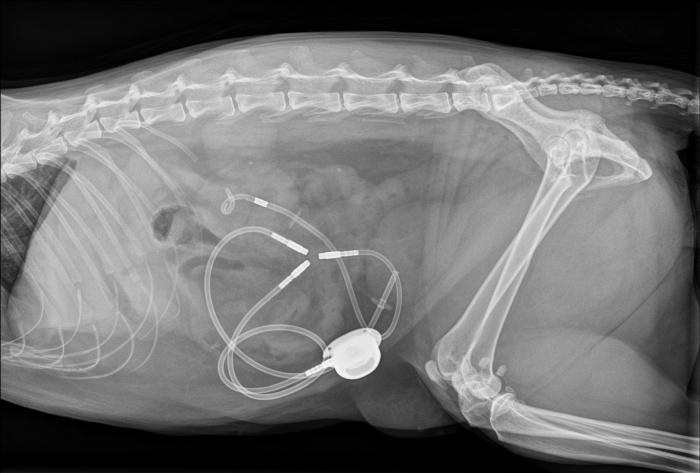

- Suelen requerir intervención quirúrgica urgente, por ejemplo, mediante la colocación de stents o bypass ureterales subcutáneos (SUB) (Figura 1-2) (ambas imágenes han sido cedidas por el Servicio de Diagnóstico por Imagen del Hospital Veterinario Puchol), pero también requieren una estabilización mínima previa a la anestesia.